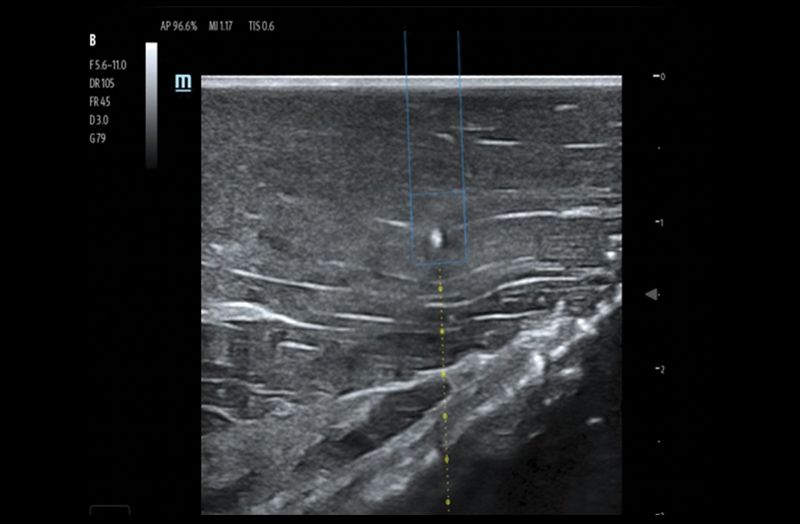

Ultrasound Reimagined

Advanced Technologies

Clinical Certainty Within Reach